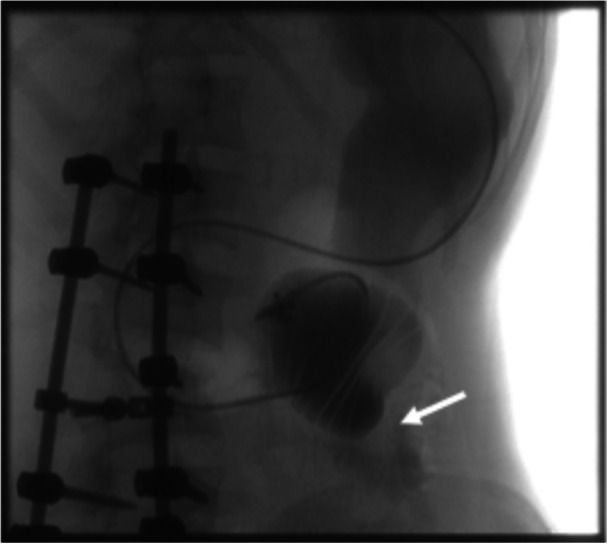

Traumatic bowel injury is an uncommon injury pattern that can have a delayed presentation after an initial trauma hospitalization and present to pediatricians with nonspecific symptoms. This syndrome is often missed and can mimic other common gastrointestinal conditions. Our case presents a previously healthy 16-year-old girl with recent trauma admission who re-presented to the hospital with a presumed superior mesenteric artery syndrome and had a mixed response to initial management. Given persistent symptoms despite standard care, subsequent management consisted of an exploratory laparotomy that led to findings of a strictured segment of the bowel that was resected and led to clinical recovery. These patients can initially present with normal imaging and have an evolving inflammatory-mediated process due to microvascular injury and abscess formation. These injuries should be included in the differential diagnosis of patients with nausea, vomiting, abdominal pain, weight loss, and fever in the setting of recent blunt abdominal trauma.